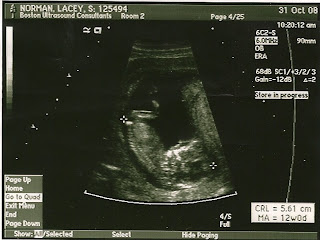

Here are some pictures from the ultrasound. The first one is of the arm and hand (we could see all five fingers by the way!) and the last three are profile shots. I'll be posting belly shots soon and I'll post the sex after next week. Merry Christmas to all of our friends and family - we miss you!!